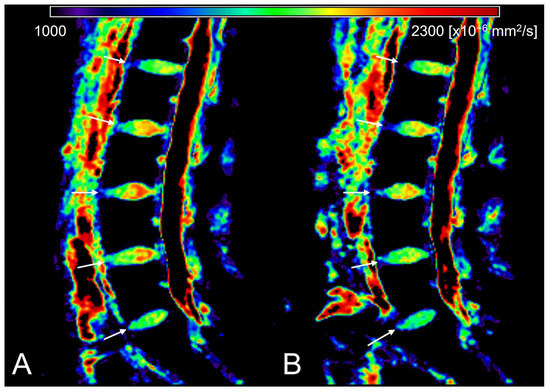

| ADC [×10−6 mm2/s] | Morning | 1784.633 ±124.527 | 1744.867 ±84.098 | 1810.641 ±116.277 | 1849.257 ±89.464 | 1776.74 1 ± 168.954 | 1738.196 ±127.040 |

| (1328.54 − 2005.07) | (1633.64 − 1909.40) | (1507.33 − 2005.07) | (1689.26 − 1986.82) | (1328.54 − 1922.59) | (1345.55 − 1872.46) | ||

| Evening | 1761.456 ±134.130 | 1728.474 ±63.042 | 1769.122 ±142.371 | 1824.274 ±103.646 | 1751.606 ±183.742 | 1733.224 ±142.604 | |

| (1247.46 − 1972.04) | (1605.50 − 1849.15) | (1356.50 − 1926.90) | (1602.80 − 1972.04) | (1247.46 − 1897.12) | (1376.50 − 1912.06) | ||

| N | 84 | 17 | 17 | 17 | 16 | 17 | |

| p | <0.001 | 0.101 | 0.002 | 0.025 | 0.056 | 0.741 | |